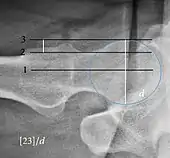

| Alpha angle | ![]() |

Degree of bulging of the femoral head-neck junction: In normal conditions there is a symmetric concave contour at the junction of the femoral head and neck. Loss of this concavity or bone bulging may lead to cam type impingement. The degree of this deformity can be measured by the alpha angle. Although it can be measured in the cross-lateral view, the 45° Dunn view is considered more sensitive and the frog leg view more specific in determining pathologic values. |

|